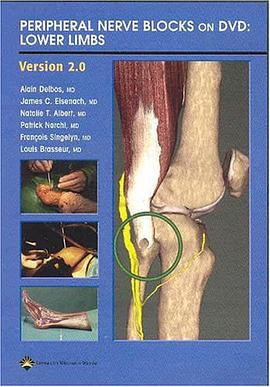

The Self-Directed Teacher pdf epub mobi txt 电子书 下载 Peripheral Nerve Blocks on DVD pdf epub mobi txt 电子书 下载

Peripheral Nerve Blocks on DVD pdf epub mobi txt 电子书 下载